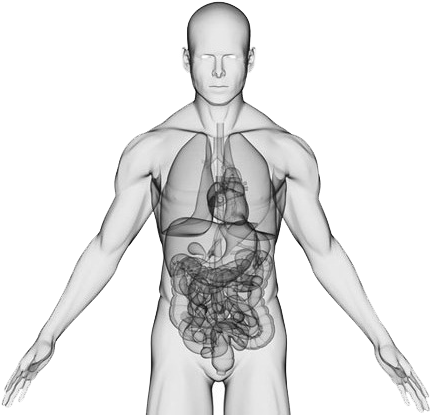

Download Hd Body Centrum Inside Human Body Png Transparent Png Image Nicepng Com

www.nicepng.com

www.nicepng.com